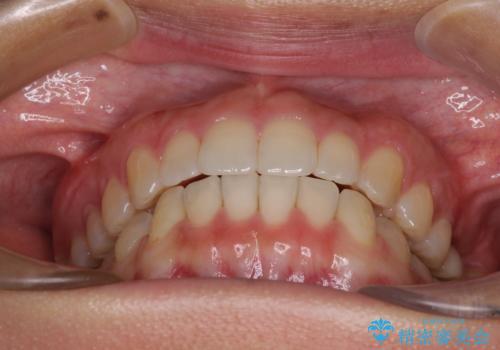

インプラントによる補綴治療とインビザライン矯正

- 抜歯が必要と診断された奥歯を気にして来院された患者様です。

抜歯の上インプラントによる補綴治療を行うこととなりましたが、前歯の叢生も気になるとのことで並行して矯正治療を行うこととしました。

歯列不正は軽微であったので、インビザラインによる矯正治療とし、矯正治療中にインプラント埋入を行う予定としました。

痛みがないので、ボロボロのまま放置していましたが、抜歯後は汚れが溜まりにくくなりスッキリとしたようです。

前歯のデコボコも解消され、ブラッシングが楽になりました。